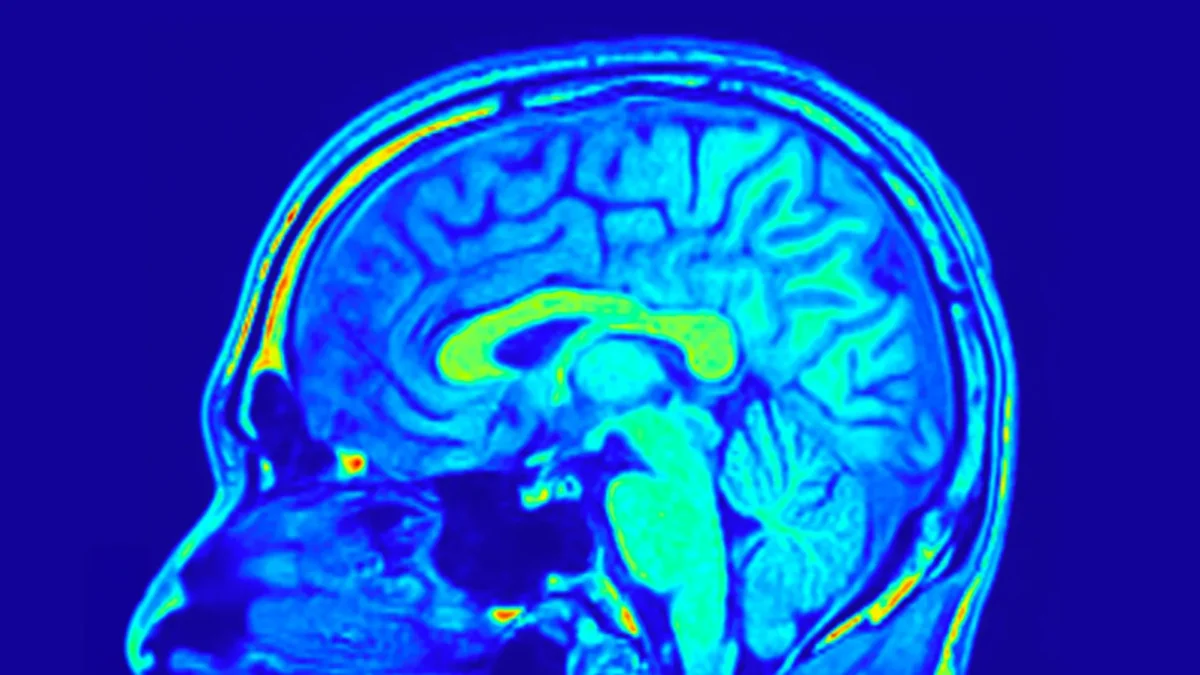

پژوهشگران با تحریک میتوکندری موفق به بازگرداندن حافظه حیوانات مبتلا به زوال عقل شدند.

به گزارش تکناک، میتوکندریها ساختارهای ریز درون سلولهای ما هستند که انرژی حیاتی بدن را تأمین میکنند. این پژوهش تازه که در مجله Nature Neuroscience منتشر شده است، به سرپرستی محققان موسسه ملی تحقیقات پزشکی انسرم (Inserm) و دانشگاه بوردو با همکاری دانشگاه مونکتون کانادا، برای نخستینبار رابطه علت و معلولی بین اختلال عملکرد میتوکندری و مشکلات مغزی را در بیماریهای عصبی تخریبکننده آشکار کرده است. این یافتهها میتواند مسیر درمانهای زوال عقل و آلزایمر را متحول کند.

میتوکندریها همانند باتریهای سلولی عمل و انرژی لازم را برای فعالیت طبیعی سلولها تولید میکنند. مغز یکی از پرمصرفترین اندامها از نظر انرژی است و نورونها برای ارسال پیامهای عصبی به شدت به عملکرد میتوکندری وابسته هستند. زمانی که عملکرد میتوکندری دچار اختلال شود، نورونها انرژی کافی برای فعالیت درست را از دست میدهند.

در بیماریهای عصبی تخریبکننده مانند آلزایمر، اختلال در عملکرد نورونها و کاهش فعالیت میتوکندری قبل از مرگ سلولی مشاهده میشود. تاکنون ابزار مناسبی برای اثبات این موضوع که کاهش عملکرد میتوکندری علت بیماری است یا نتیجه آن، وجود نداشت.